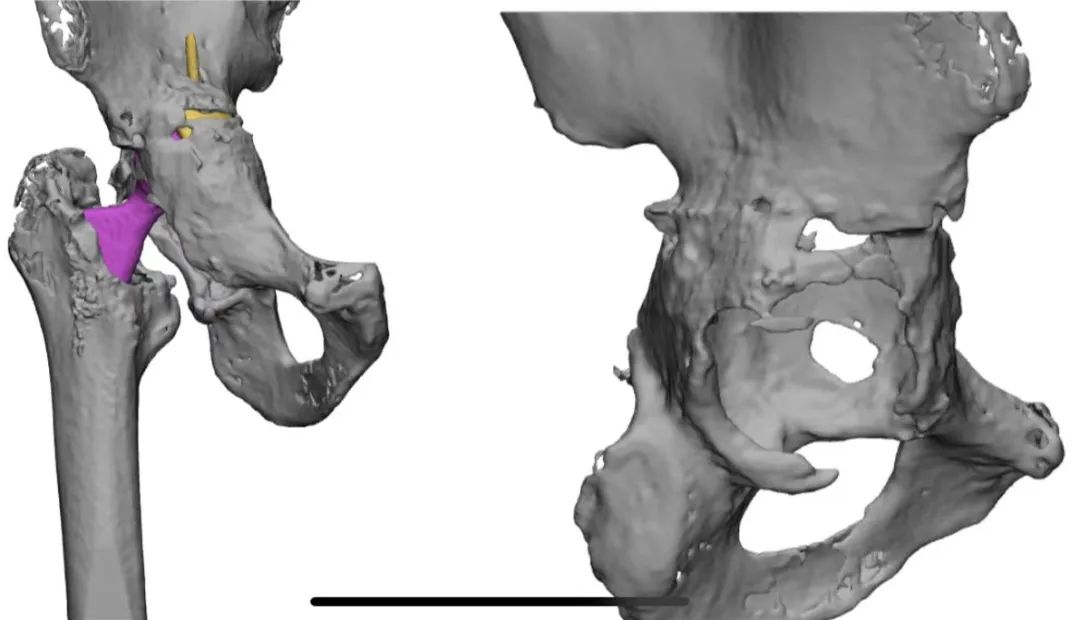

3D打印对精准手术保驾护航

术前,手术团队运用3D打印技术,精准打印患者骨缺损情况,并个体化设计手术方案,选择人工假体组件;体外模拟手术,以确保手术过程精准、顺利进行。

3D设计照片